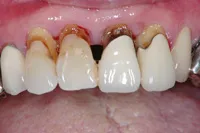

むし歯による前歯欠損の為来院されたケース

■治療前

■歯の根の引き上げ

■治療後

治療のポイント

歯の根の位置を引き上げ、抜歯。その日にインプラント治療へ。

自然の歯と変わらない審美性を取り戻し、非常に満足されています。

| 主訴 | 上顎の真ん中の歯が折れた |

| 治療方法 | 歯の根を引き上げることにより、増骨するので、その後1本のインプラントを埋入し治療した |

| 治療期間 | 約1年 |

| 通院回数等 | 10回 |

| 費用 | 550,000円(税込) |

| リスク・副作用 | 外科治療なしで増骨させた為、治療期間が長くなった |